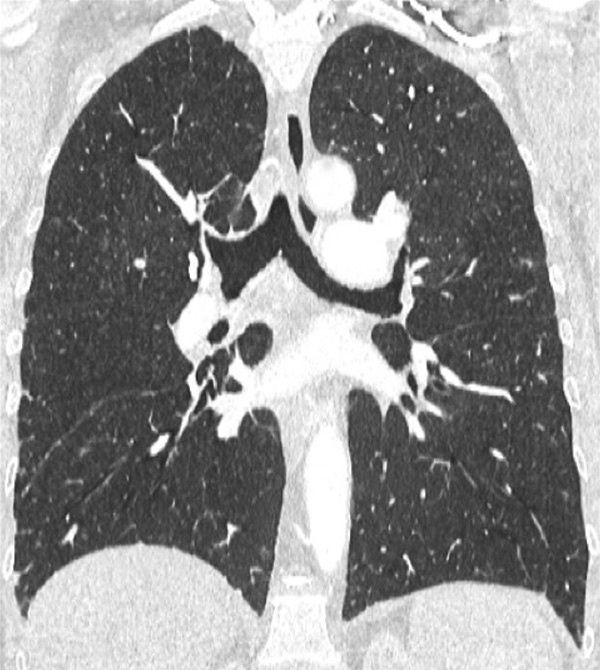

Figure 4

Peripheral chronic thromboembolic pulmonary hypertension (CTEPH). No visible pulmonary artery emboli on standard CTPA are seen (arrows) (A) but a wide perfusion defect on the perfusion maps is depicted (B) and allows the diagnosis of peripheral CTEPH.